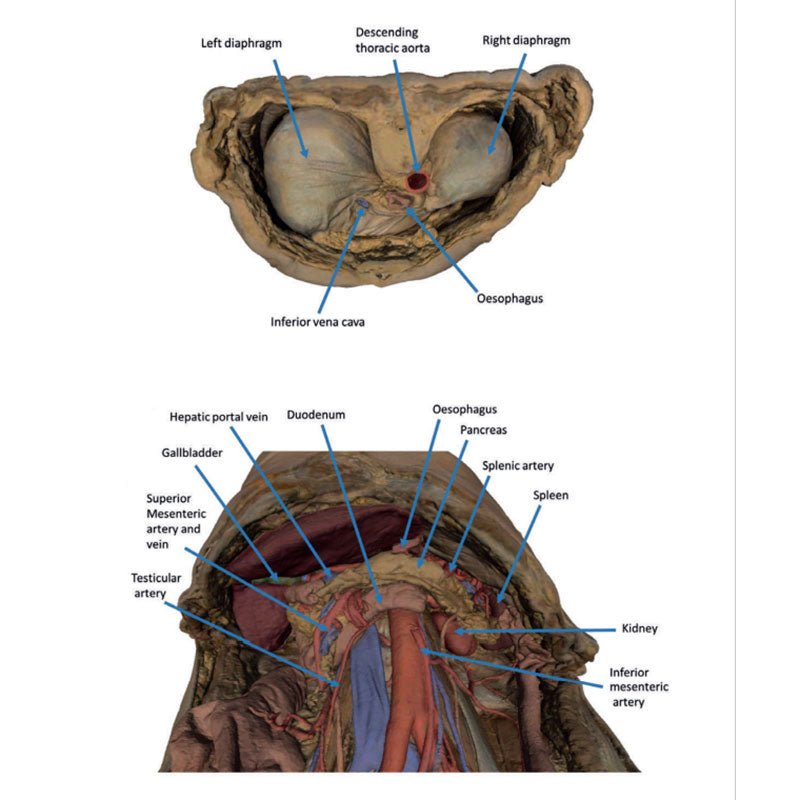

The diaphragm

On the superior aspect of the model the diaphragm is preserved, and while slightly distorted due

to removal of the thoracic ribs through dissection, both domes and costodiaphragmatic recesses can be

appreciated. The fibrous pericardium is present on the superior surface of the central tendon, with the terminal

part of the inferior vena cava visible in the caval foramen. Just lateral to caval foramen is the oesophagus

within the oesophageal hiatus, and then the descending thoracic aorta approaching the aortic hiatus just ventral

to the thoracic vertebrae.

The epigastric and hypochondriac regions

Within the abdomen, the anterior abdominal wall, greater omentum, and

much of the gastrointestinal tract has been removed alongside the parietal peritoneum over the posterior

abdominal wall to expose retroperitoneal organs and structures. In the superior abdomen, the terminal portion of

the oesophagus has been retained and can be seen entering the cavity just lateral to the left lobe of the liver.

The removal of the stomach has exposed the extent of the pancreas from the head (positioned within the arc of

the duodenum) to the tail extending to the capsule of the spleen preserved in the left hypochondrium. Superior

to the pancreas, the splenic artery and common hepatic arteries can just be observed spanning across the narrow

space between the pancreas, diaphragm and liver. The splenic follows its archetypical ‘tortuous route’

towards the spleen, and strongly divides prior to reaching the hilum (and adjacent to the splenic vein). The

common hepatic can be seen dividing into the gastroduodenal (visible again as a cut vessel just inferior to the

duodenum) and giving off the right gastric artery; these vessels lie superficial relative to the hepatic portal

vein. The superior mesenteric artery and vein can be seen passing anteriorly near the head of the pancreas and

horizontal part of the duodenum, and the retained ileocolic artery can be traced to the caecum of the large

intestine in the lower right quadrant of the abdomen. The inferior mesenteric vein can be, in part, appreciated

arising from the retained superior rectal vein ascending from the undissected true pelvis and spanning across

the superficial aspect of the descending thoracic aorta.

Inferior to the liver the gallbladder can be viewed just between the right and left anatomical lobes. On the left, the passage of the renal artery and vein can be seen just deep to the pancreas, and the ureters can be observed descending from the partially exposed kidney across the superficial surface of the exposed psoas major and minor muscles.